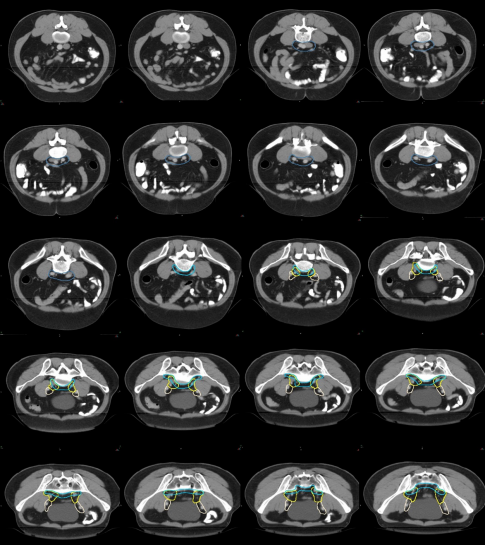

GTV 及 GTVnd 勾畫定義

a) GTV(紅色)通過對比定位 MR 圖像,在 CT 定位圖像完成 GTV 的勾畫(圖 1)。

圖 1 直腸癌 GTV 勾畫示例

b) GTVnd(粉色) :轉移淋巴結在診斷磁共振或定位磁共振圖像顯示清楚,可參考并輔助在 CT 定位圖像完成 GTVnd 的勾畫(圖 2-圖 4)。

圖 2 直腸癌俯臥位直腸系膜區淋巴結勾畫示例

圖 3 直腸癌俯臥位骶前區淋巴結勾畫示例

圖 4 直腸癌俯臥位淋巴引流區淋巴結勾畫示例